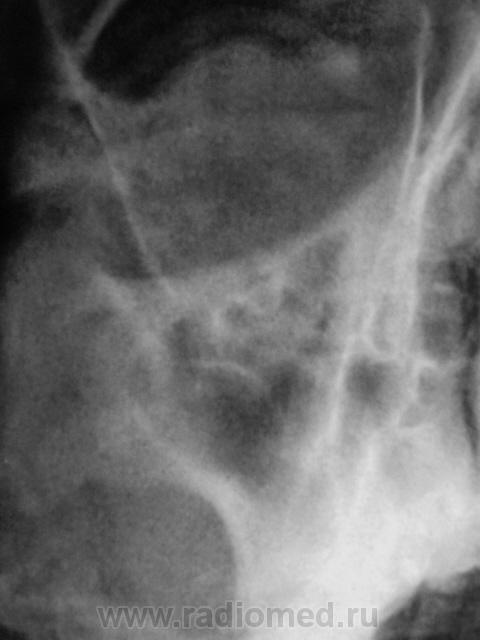

справа вроде есть пристеночное утолщение слизистой оболочки по медиальной стенке, а слева толи киста толи полип толи отек, контроль в динамике